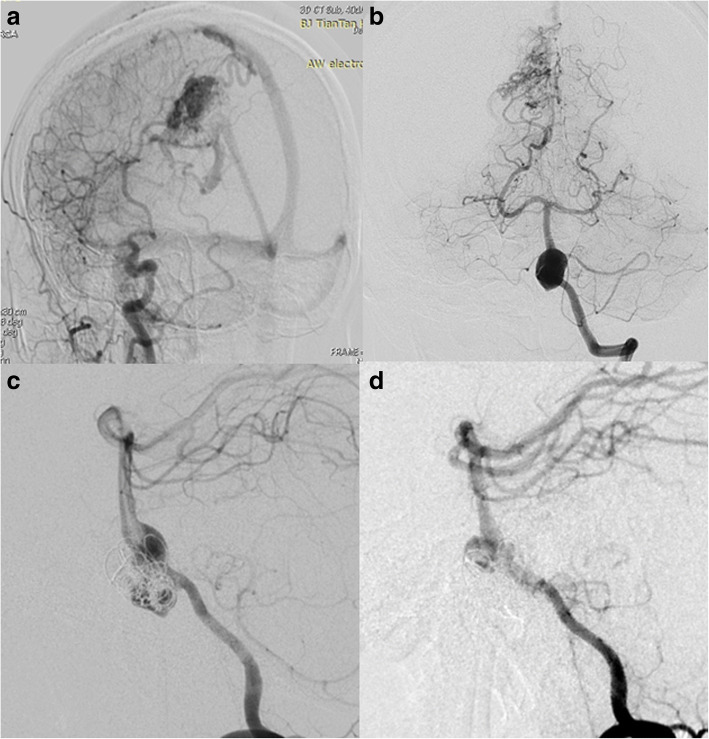

Fig. 6.

Case No. 6, a V-B junction aneurysm (a) treated by overlapping 2 longest PEDs (4.25 mm*35 mm) (b) to enhance the flow diversion effect and further occluded the contralateral VA with coils (c). Note that the distal PED covered the mid-basilar perforators

We treated 3 cases of aneurysm with concomitant DAVF either in one single session (Case No.7) or by a staged procedure (Case No. 8, Case No.9). Case No. 7 was a 56-year-old female with a transverse sinus DAVF whose feeding arteries were from right VA (Fig. 7a), right petrosquamous branch of ICA (Fig. 7b), right middle meningeal artery and right occipital artery (Fig. 7c). The aneurysm measured 2.9 mm*3.9 mm and was located near the origin of the right ophthalmic artery. We deployed a PED (4.0 mm*16 mm) to treat the aneurysm without further coiling it (Fig. 7d). We applied the Chapot’s technique to protect the sinus during embolization of the DAVF through the right middle meningeal artery (Fig. 7e), then we deflated the Copernic balloon (Balt, France) and embolised the residual part of fistula through the right occipital artery. The 6 month follow up demonstrated complete occlusion of the aneurysm (Fig. 7f) and minimal residual of DAVF. We performed staged procedures for Case NO.8 and NO.9, we first treated the anterior fossa DAVF (Case NO.8) and transversus sinus DAVF (Case NO. 9) with Onyx-18 (ev-3, USA). Three months later, when complete occlusion of the fistula was confirmed, we performed PED for both patients. For the aneurysm of Case 9, its patent artery gave branch to feed the fistula, namely, the ipsilateral petrosquamous branch. While for case NO. 8, the right vertebral artery aneurysm was not correlated with any of the feeders of the anterior fossa DAVF. None of the 3 patients experienced any neurological complications, the aneurysms all completely occluded within short-term angiographic follow-up.

Fig. 7.

Case No. 7 was a 56-year-old female with a transverse sinus DAVF whose feeding arteries were from right VA (a), right petrosquamous branch of ICA (b), right middle meningeal artery and right occipital artery (c). The aneurysm on ophthalmic segment of ICA (b, blue arrow) was treated by a PED without further coiling and was incompletely occluded (d, blue arrow). The fistula was embolised using the Chapot’s technique (e). The 6 month follow up demonstrated complete occlusion of the aneurysm (f)

Case No. 4 was 34-year old female complained a gradually aggravated headache for 3 months. DSA showed a V-B junction aneurysm. Besides the aneurysm, the patient suffered from an AVM (Spetzler-Martin 3) that received feeding arteries both from the anterior posterior circulation (Fig. 4a, b). We deployed the PED (4.25 mm*25 mm) from the lower 1/3 of basilar artery to the left VA and further coiled the aneurysm loosely to achieve favorable stasis of flow (Fig. 4c). 3 months follow up indicated incomplete occlusion of the aneurysm (Fig. 4d). Case No. 5 was an 8-year-old girl presented with ataxia, vomiting and nausea. DSA indicated a large V-B junction dissecting aneurysm (Fig. 5a). Learned from the experience of case 4, we decided to telescoping two PEDs (4.25 mm*35 mm) to achieve a better flow diversion effect. Control angiography suggested that there was no apparent stasis of angiographic agent due to the persistent blood flow from the contralateral VA. So we decided to coil the aneurysm and concomitantly to occlude the aneurysm with a detachable balloon (Balt, France) (Fig. 5b). The patient recovered from general anesthesia smoothly and discharged without any neurological deficit. 3 months follow up angiography indicated a certain degree of decrease in size and the patient was free from any symptom, yet the aneurysm was still partially embolised (Fig. 5c). So, knowing that the V-B junction aneurysm is quite refractory in nature, we treated case No. 6 (Fig. 6a) By overlapping 2 longest PEDs (4.25 mm*35 mm) to enhance the flow diversion effect and further occluded the contralateral VA with coils (Fig. 6b, c). It is inevitable to cover the perforating branches of basilar artery if you chose a 35 mm long PED. The patient experienced transient visual loss of both eyes, however, the patient completely recovered from these symptoms one day after operation. This patient is still on follow-up.